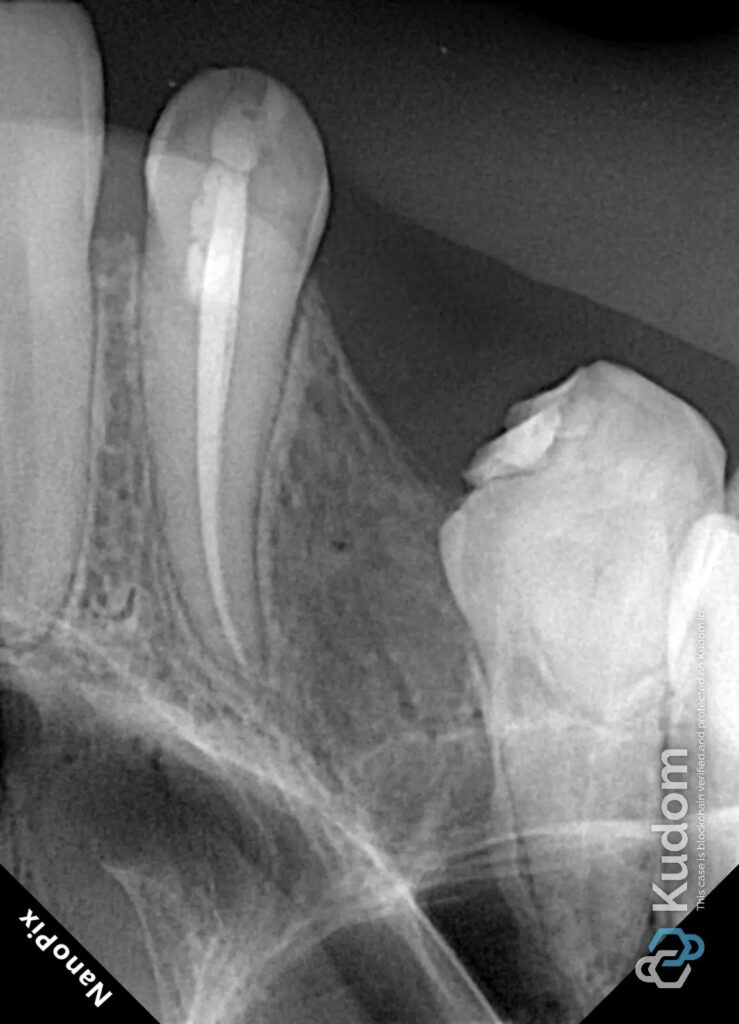

The patient presented with symptoms and radiographic findings suggestive of persistent apical pathology associated with an upper right molar previously treated endodontically. Adjacent to this tooth, the maxillary canine exhibited an ill-fitting crown with marginal discrepancies and signs of periodontal inflammation.

Clinical and radiographic assessment revealed:

- Inadequate prior root canal obturation in the molar

- Suspicion of a missed MB2 canal

- Coronal leakage potential due to restorative compromise

- Poor marginal adaptation of the canine crown, contributing to localized gingival inflammation